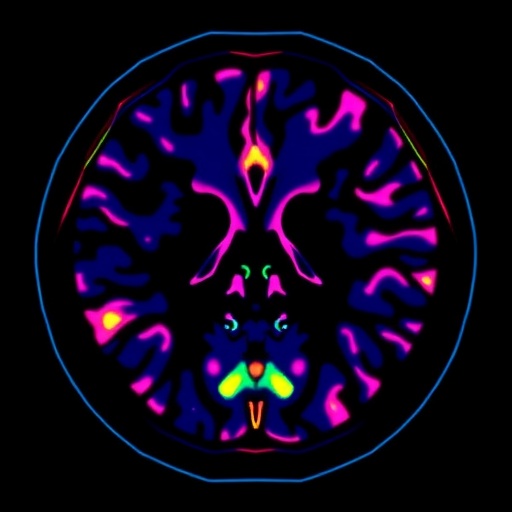

An intriguing aspect of the research is the incorporation of explainability tools that translate the AI’s internal reasoning into human-readable formats. For instance, heatmaps generated by the model visually highlight regions within the lesion that are most predictive of malignancy, thereby directing the radiologist’s attention to critical imaging features such as irregular borders or heterogeneous enhancement patterns. This symbiotic interaction between machine and clinician fosters trust and facilitates the integration of AI assistance into everyday diagnostic workflows.

The implications of this AI advancement extend beyond breast imaging. The methodology of combining interpretability with clinical-grade performance could serve as a blueprint for other medical imaging domains where false-positive rates are high. Radiological disciplines such as prostate MRI, lung nodule detection, and brain tumor classification stand to benefit from similar AI-enhanced stratification techniques, promising a broader impact on diagnostic precision and patient care standards.